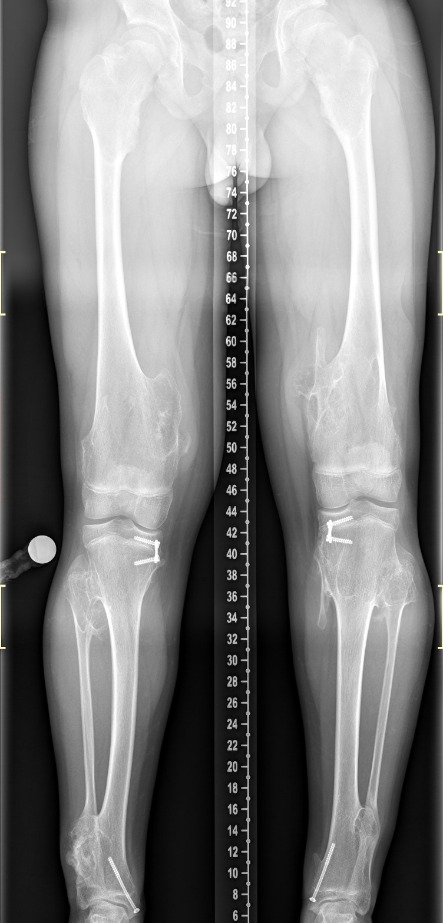

Πολλαπλά οστεοχονδρώματα

Οι εικόνες απεικονίζουν περιστατικό με πολλαπλά οστεοχονδρώματα, το οποίο χειρουργήθηκε από τον Δρ. Ζένιο.

Προ-εγχειρητικά

Μετ-εγχειρητικά

Νόσος του Όλιερ

Οι εικόνες απεικονίζουν ένα περιστατικό με την Νόσο του Όλιερ, όπου παρουσίαζε κοντύτερο αριστερό άκρο. Χειρουργήθηκε από τον Δρ. Ζένιο με την χρήση εξωτερικής οστεοσύνθεσης.

Εξωτερική οστεοσύνθεση